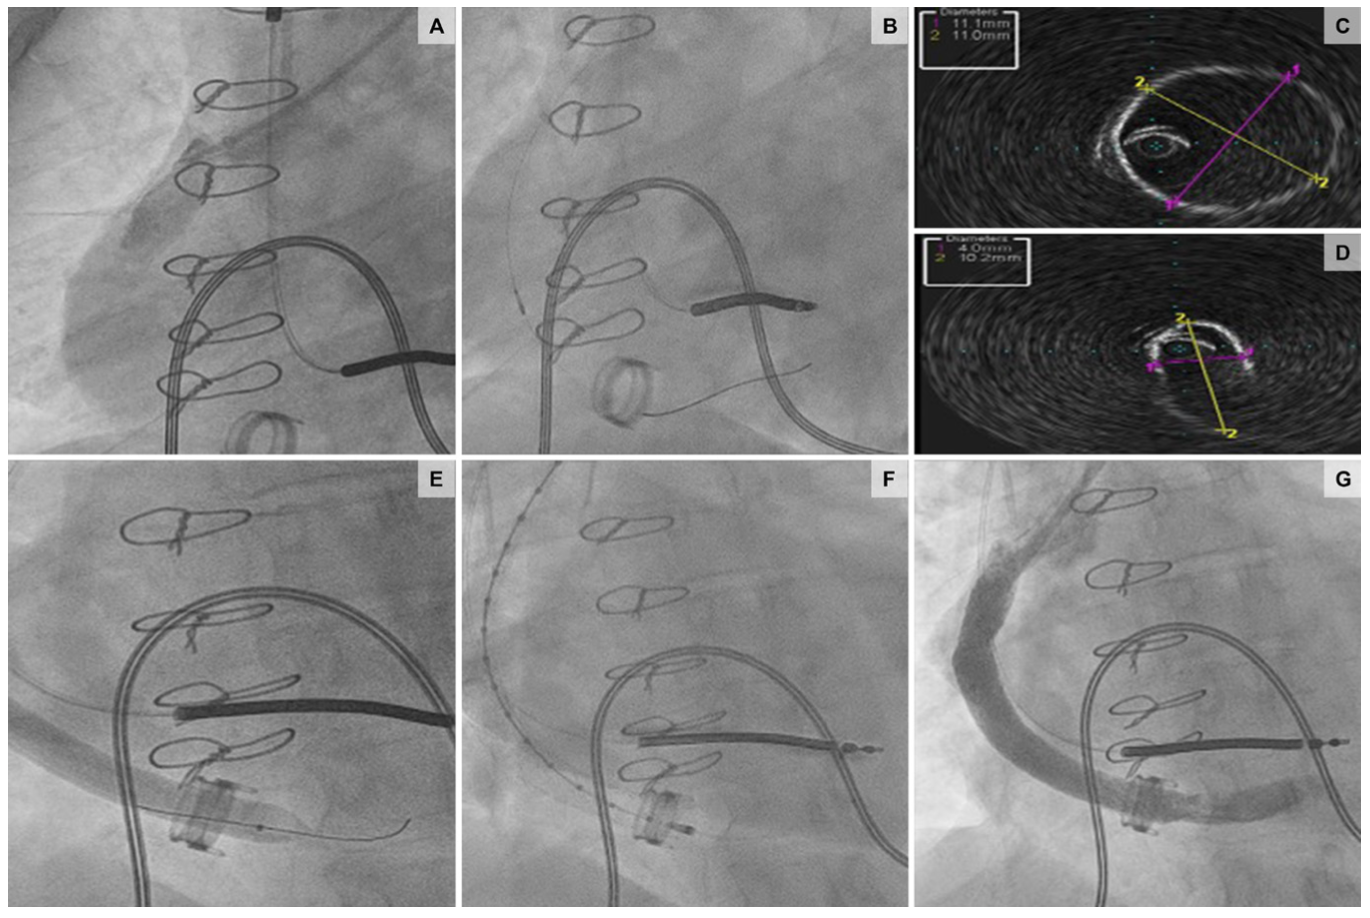

Given her body mass index of 42 kg/m2 and anterior take-off of the graft, left brachial access provided easier engagement of the outflow graft with the use of a 6-Fr multipurpose-B1 guide catheter. Intravascular ultrasound (IVUS) confirmed extrinsic compression in the mid portion of the graft, narrowing it to 4 mm. The stenosis was treated with a 10- x 60-mm balloon followed by an 11- x 79-mm VBX balloon-expandable covered stent (Medtronic). Repeat IVUS confirmed good apposition of the stent and resolution of the stenosis (Figure 4 and Figure 5; Video Series).